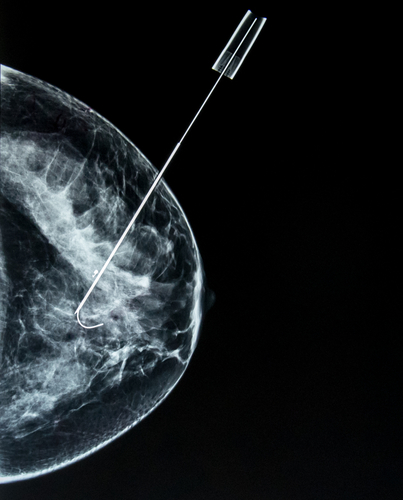

Caring for disease begins with diagnosis, you cannot treat a problem that is unknown to you. The diagnosis of breast cancer begins with identifying “a lump” whether detected by the patient or by screening mammography which detects more smaller lumps because it is more sensitive in finding the proverbial ‘needle in the haystack.’ Large lumps are easy to identify, no improvement is necessary. Because our science showed that as cancer got larger, it became ‘more aggressive,' we sought to find lumps earlier before the situation becomes more difficult or hopeless. Our ability to detect these smaller cancers increased over about eight years from 25.3 per thousand to 34.7 per thousand – about a 37% improvement [3]. In the words of the study’s author, “The change likely reflects improvements in mammography imaging technology, which permit the visualization of smaller lesions and greater detection of calcifications that result in increased cancer detection.” The underlying assumption was that earlier detection results in a better outcome and the measure of early was size. Therapy informed diagnosis and diagnosis responded. It wasn’t simply that size mattered, but for mammography, it was all that could be measured. Once identified, the lump biopsied, cancer confirmed and treatment initiated.

The treatment options were almost entirely surgical, with chemotherapy and radiation playing a supporting, adjunctive role. While ‘cure’ might be allusive, we found that early intervention resulted in improved survival, five and then ten-year cures. But for newer treatments, where chemotherapy or radiation was primary or sole treatment, our prior success necessitated a longer time-period to see better outcomes. Treatment changed at one rate, diagnosis at another, the dancers were out of sync. Another important treatment discovery was our failure to treat all small lumps successfully. Categorizing lumps by size was too heterogeneous for treatment. Size does not precisely identify biologic behavior. As best we can tell, that behavior is more closely associated with cancer's response to hormones. From treatment’s viewpoint, we now want to characterize cancers by their behavior; size is no longer the best measure. Those new criteria, because of the lag time brought by extended survival, was not established and shared for some time.

And that brings us to this current study. With the advantage of hindsight, the authors correlated the size of breast cancer at detection with the three markers we use to measure biological behavior, the grade (increasing abnormal appearance of the cells), and the response to estrogen and progesterone. This graph, from the study, captures the essence of their findings.

If you look across the categories of tumor size, the percentage of cancers with favorable biologic behavior decrease. Proof that size does matter. But when you look at the individual columns you see that size is heterogeneous regarding behavior. Some small tumors are biologically very aggressive (unfavorable in the chart) and others not so much. And the proportion of favorable tumors increases for patients over 40, the group of patients most likely to be diagnosed with cancer. The authors conclude, “Both tumor size and biologic features influence prognosis, but frequently a large favorable tumor can have a better prognosis than a small unfavorable tumor.” And nod to the future of diagnostic/prognostic factors, recognizing that “grade and receptor status are rather crude predictors of biologic features as compared with molecular assays.” Bottom line, size has lost its primary prognostic role, challenged by grade and hormone receptor status, measures that mammography cannot identify. All our effort in improving mammography to detect small has increased our difficulties [4] because our diagnostic tool is no longer dancing with our therapeutic considerations.